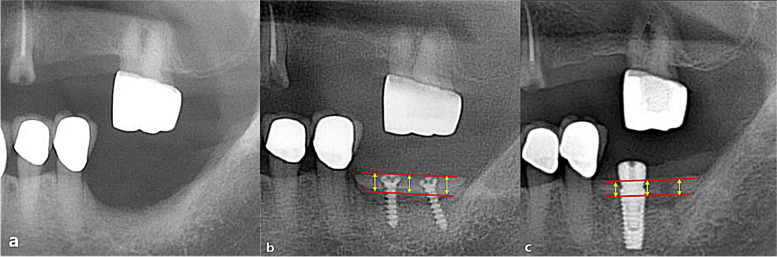

To analyze the vertical bone loss and compare the three types of autologous block bone grafts, a 50 × 50 grid was superimposed on pre and postoperative radiographic images of each patient during specific periods. Plain panoramic views were the primary imaging method used (ASAHI Roentgen® parameters of 72 ~ 76 kVp, 8 mA), and periapical views (Dentsply sirona®, parameters of 60 kVp, 6 mA, and exposure time of 0.16 ~ 0.20 s) were employed as supplementary imaging (Fig. 2). The time periods were categorized as follows: before bone augmentation (I), immediately after bone augmentation (T0), 3 months after bone augmentation (T1), 6 months after bone augmentation (T2), 12 months after bone augmentation (T3), 36 months after bone augmentation (T4), and 60 months after bone augmentation (T5). The average marginal bone height was measured and recorded for each time period. To ensure accuracy, the bone height was calculated twice to eliminate any potential statistical errors. All measurements were conducted using the PACS calibration system (PiView-Star®, version 5.0.1, Infinitt Co., Seoul, Korea).

Fig. 2.

Measurement of the vertical amount of bone gain and resorption amount. a Vertical alveolar bone gain was measured using an immediate post-operative radiograph, calculating the distance between the adjacent tooth and the top of the grafted bone or the head of the screw. b Three months after augmentation, the extent of vertical bone resorption was assessed

Vertical bone gain

The amount of vertical bone gain was assessed by measuring the distance between the uppermost and lowermost margins of the grafted block bone at the mesial, middle, and distal regions, with the adjacent tooth serving as the reference point (Fig. 2). Subsequently, the average value was calculated. To ensure reliability, the initial preoperative bone height was measured twice, yielding an intraclass correlation coefficient of 0.958.

Vertical bone resorption

The distance between the uppermost point of the block bone and the implant shoulder (or the top of the screw head) at the mesial, middle, and distal regions were measured at each time period, and the average value was calculated.

After the insertion of dental implants, the magnification factor was determined based on the length of the implant fixture. This magnification factor was then applied to each patient, and a correction value was obtained by dividing the magnification factor by the actual measurement value.